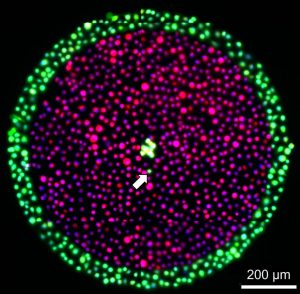

Example REU Project: Two REU students will learn to fabricate antigen-loaded nanoparticles (200-800 nm) using CPH:SA and CPTEG:CPH copolymers. The antigens of interest include ovalbumin, F1-V (plague antigen), influenza hemagglutinins, and rPA (recombinant protective antigen against anthrax). The students will learn to characterize these nanoparticles using electron microscopy and a Zetasizer (for size distribution). One REU student will study how the blank nanoparticles (i.e., no antigen) are uptaken by antigen presenting cells of the immune system using confocal laser scanning microscopy. The second REU student will immunize mice with these antigen-loaded nanoparticles with the appropriate controls. The immune response in these animals will be characterized using both antigen-specific antibody responses and T and/or B cell proliferative responses. Together, all these studies will provide molecular and cellular information about how polymer chemistry enhances and activates host immune responses. This project will expose the students to nanotechnology, materials science, biochemistry, animal studies, and applied immunology.